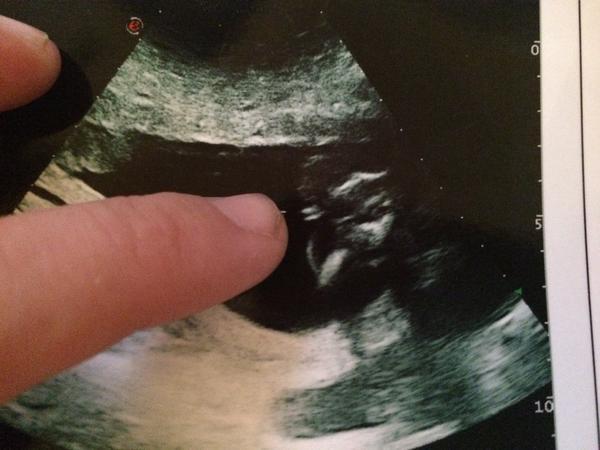

@lala1501 No ja tam vidím mini dúšika, aký je to test?

@kythos21 Ahoj,podľa mňa dievčatko 🙂 pipik keby tam je tak ten trčí 🙂 a vyzerá to inak 🙂